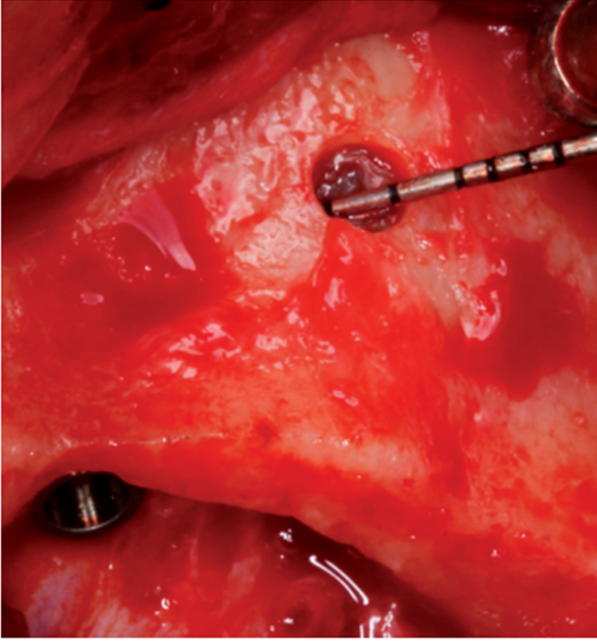

A técnica all-on-four foi realizada instalando dois implantes anteriores na região da pré-maxila, de acordo com a disponibilidade óssea, enquanto que os dois implantes posteriores foram instalados tangenciando a parede mesial do seio maxilar localizados através de pequeno acesso ao seio maxilar e localização clínica da parede (Figura 1).

Quando necessário, o rebordo foi regularizado através de osteotomia. Os implantes foram subfresados com o objetivo de aumentar a estabilidade primária dos implantes. O tamanho e diâmetro dos implantes foi escolhido de acordo com a disponibilidade óssea.

Os implantes foram instalados com auxílio de contra-ângulo cirúrgico montado em motor elétrico com um torque de até 35 Ncm. Após, os implantes foram posicionados com torquímetro cirúrgico manual (Implacil De Bortoli / São Paulo / Brasil), sendo que o torque foi medido no final da instalação da fixação. Os implantes foram instalados em nível ósseo (Figura 2).